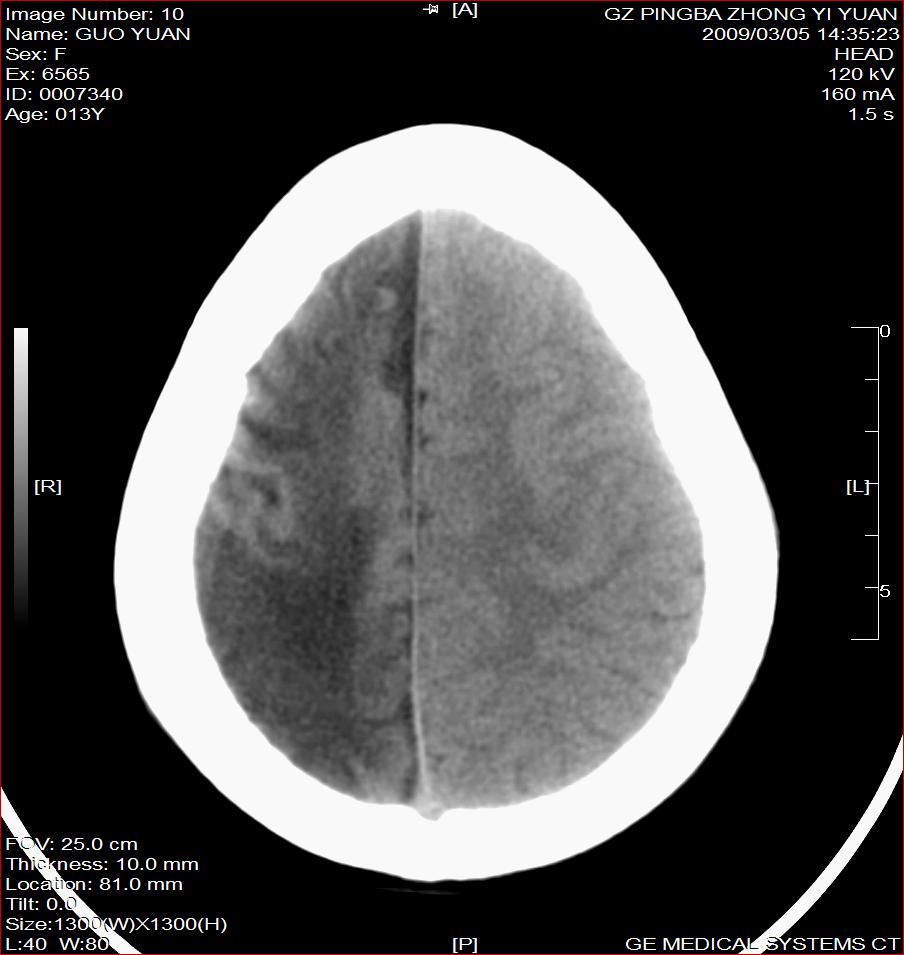

以下是引用杀毒软件在2009-3-6 17:32:00的发言:[br]右侧额颞顶部脑沟裂增宽,颞顶部楔形稍低密度影,侧脑室体部明显增宽,余脑实质内未见异常,中线结构居中。[br][br]考虑---右侧大脑半球发育不良并脑沟裂发育畸型可能性大

以下是引用随光逐影在2009-3-6 18:35:00的发言:[br]1)考虑右侧幕上半球发育不良并脑软化灶。2)双侧额部头皮软组织肿胀。